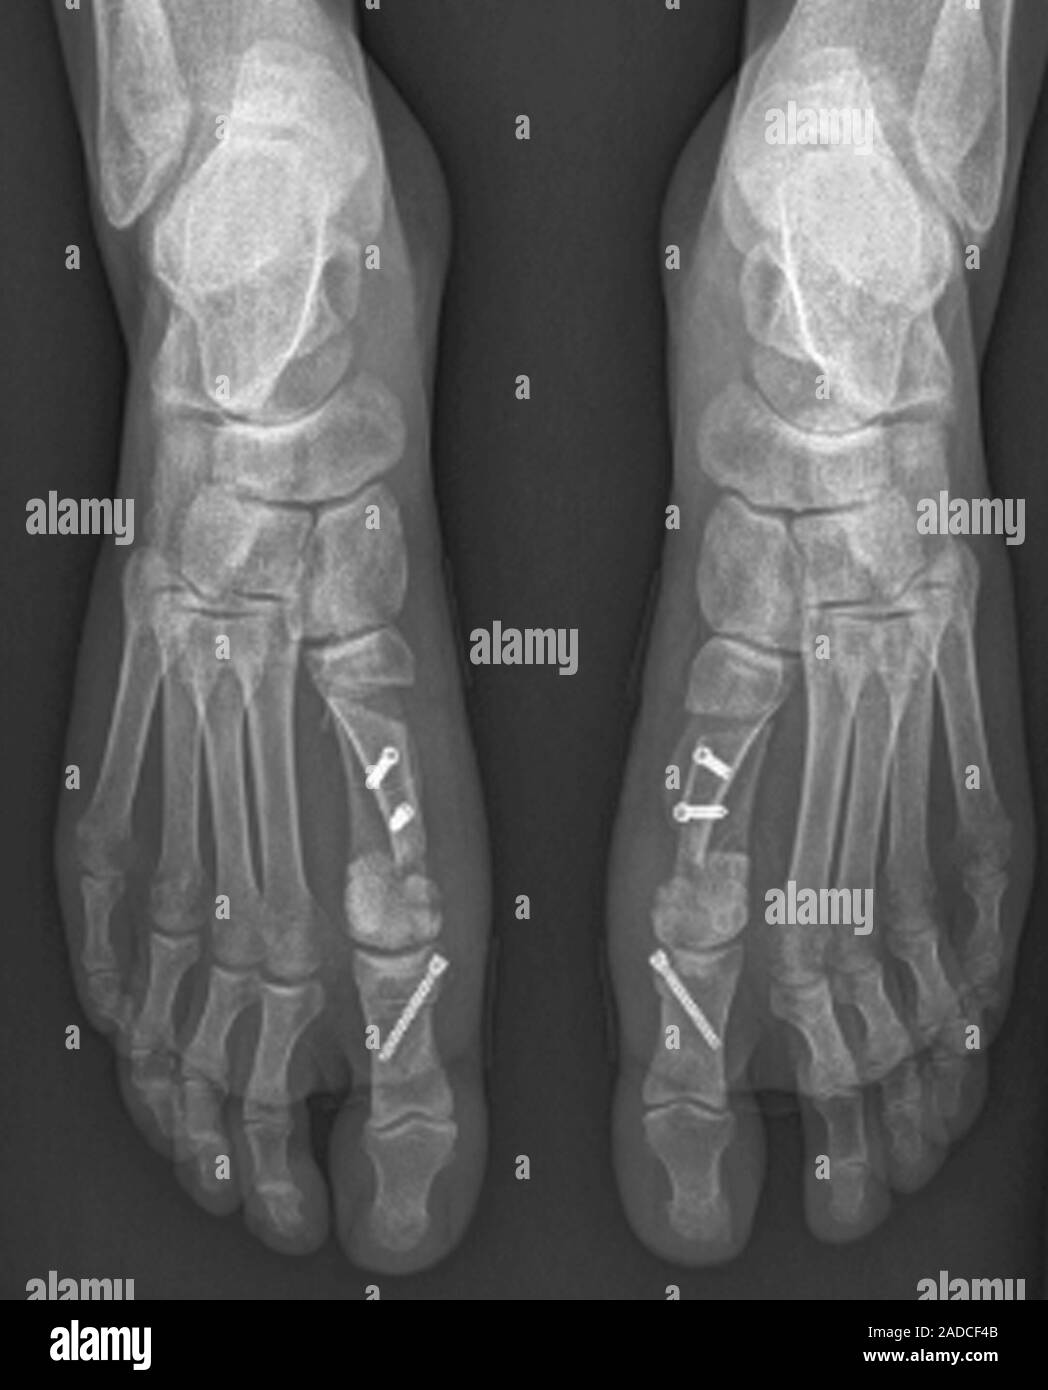

From www.alamy.com

Bunion surgery. Bilateral frontal Xray of the feet of a 24yearold Does Bunion Surgery Require Screws  There are no guarantees that a bunion surgery will fully. Some services may not be offered in our offices. Your doctor will guide you through. This guide is for informational purposes only. There are multiple techniques, but all involve cutting the bones.   the corrective surgery for bunion is known as a metatarsal osteotomy or bunionectomy.   there are four. Does Bunion Surgery Require Screws.